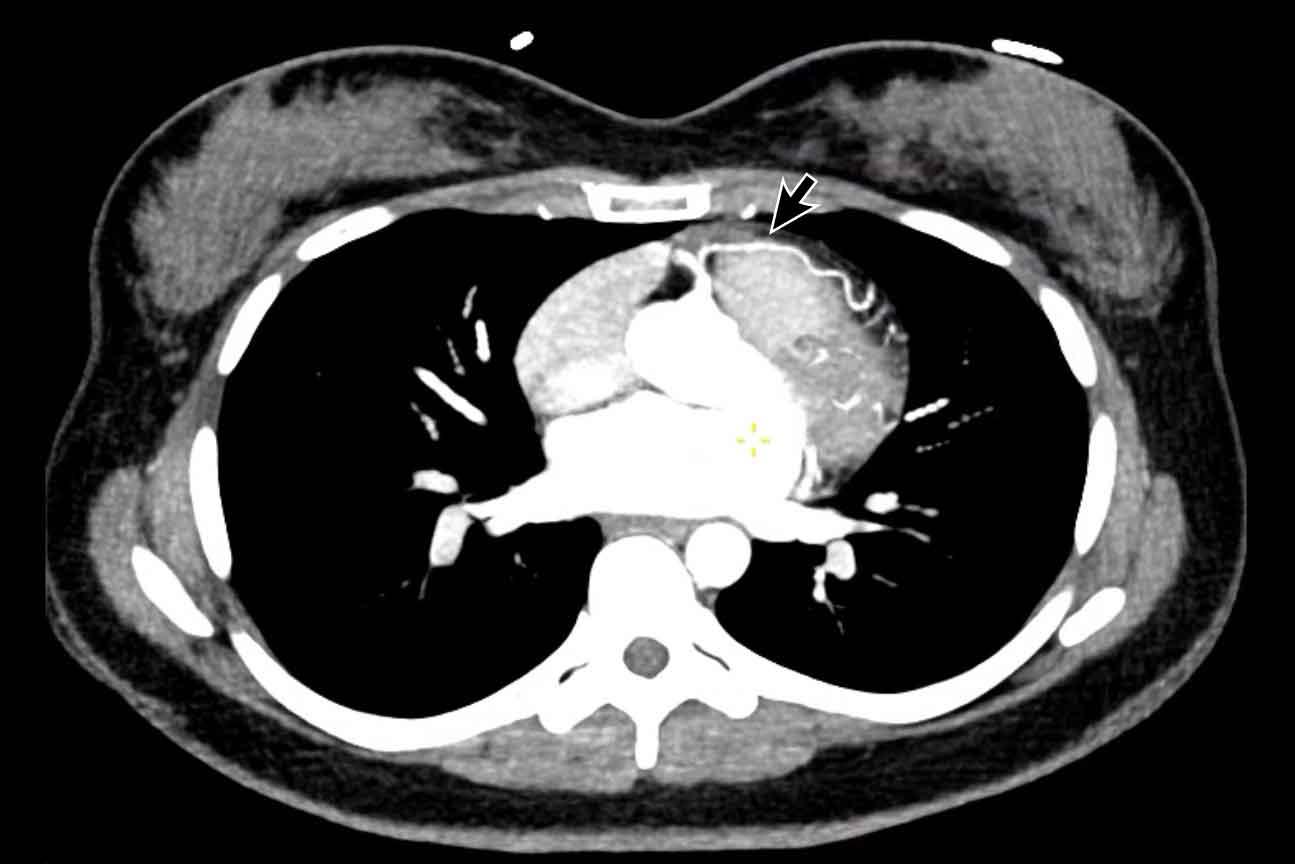

Hình ảnh

Nhĩ trái giãn.

Có huyết khối trong tiểu nhĩ trái (mũi tên) lan rộng về phía nhĩ trái (đầu mũi tên).

Tại tiểu nhĩ trái, thường gặp khó khăn trong chẩn đoán phân biệt hình ảnh giữa huyết khối và hiện tượng ngấm thuốc không hoàn toàn do dòng chảy chậm, đặc biệt khi chụp ở thì thuốc sớm.

Vấn đề này có thể được giải quyết bằng cách chụp CT ở thì thuốc muộn hơn hoặc chụp ở tư thế nằm sấp.

Siêu âm tim qua thực quản được coi là tiêu chuẩn vàng.